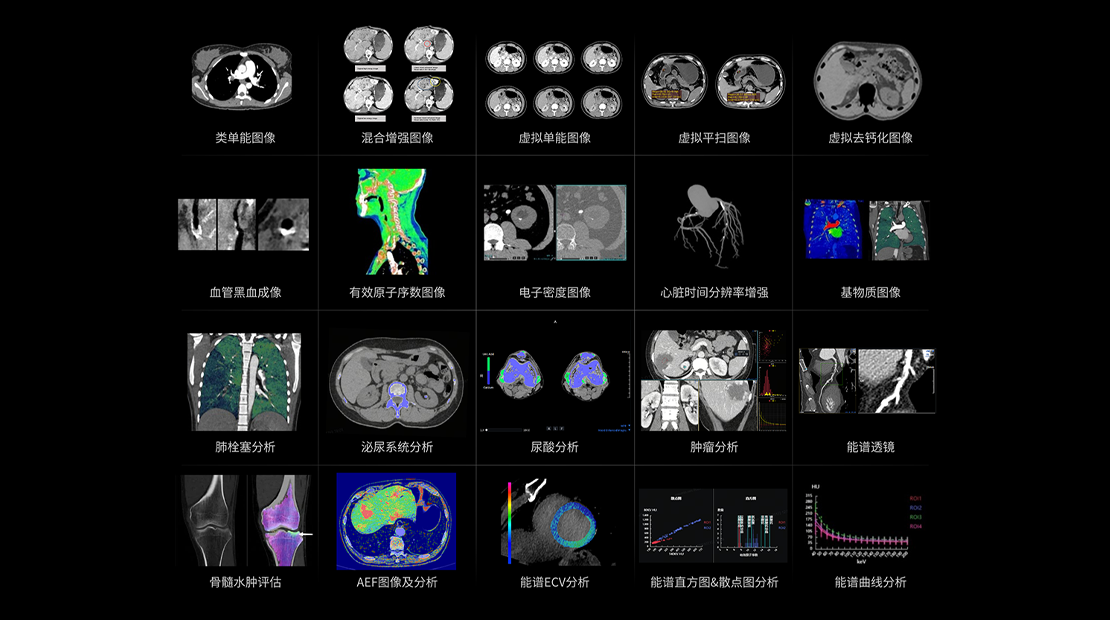

全域能谱

能谱成像可揭示丰富的物质与能量信息,其临床价值的充分释放有赖于完善高效的后处理分析平台。uCT SiriuX® 提供全面能谱高级分析工具,覆盖心血管、肿瘤、神经、骨科等多类临床场景。平台支持动脉增强分数分析(AEF)、细胞外容积分析(ECV)、肿瘤同源性分析、肺栓塞分析、骨髓水肿分析等多项评估,并提供多达10种基物质对成像,为精准诊断与科研探索提供坚实支撑。